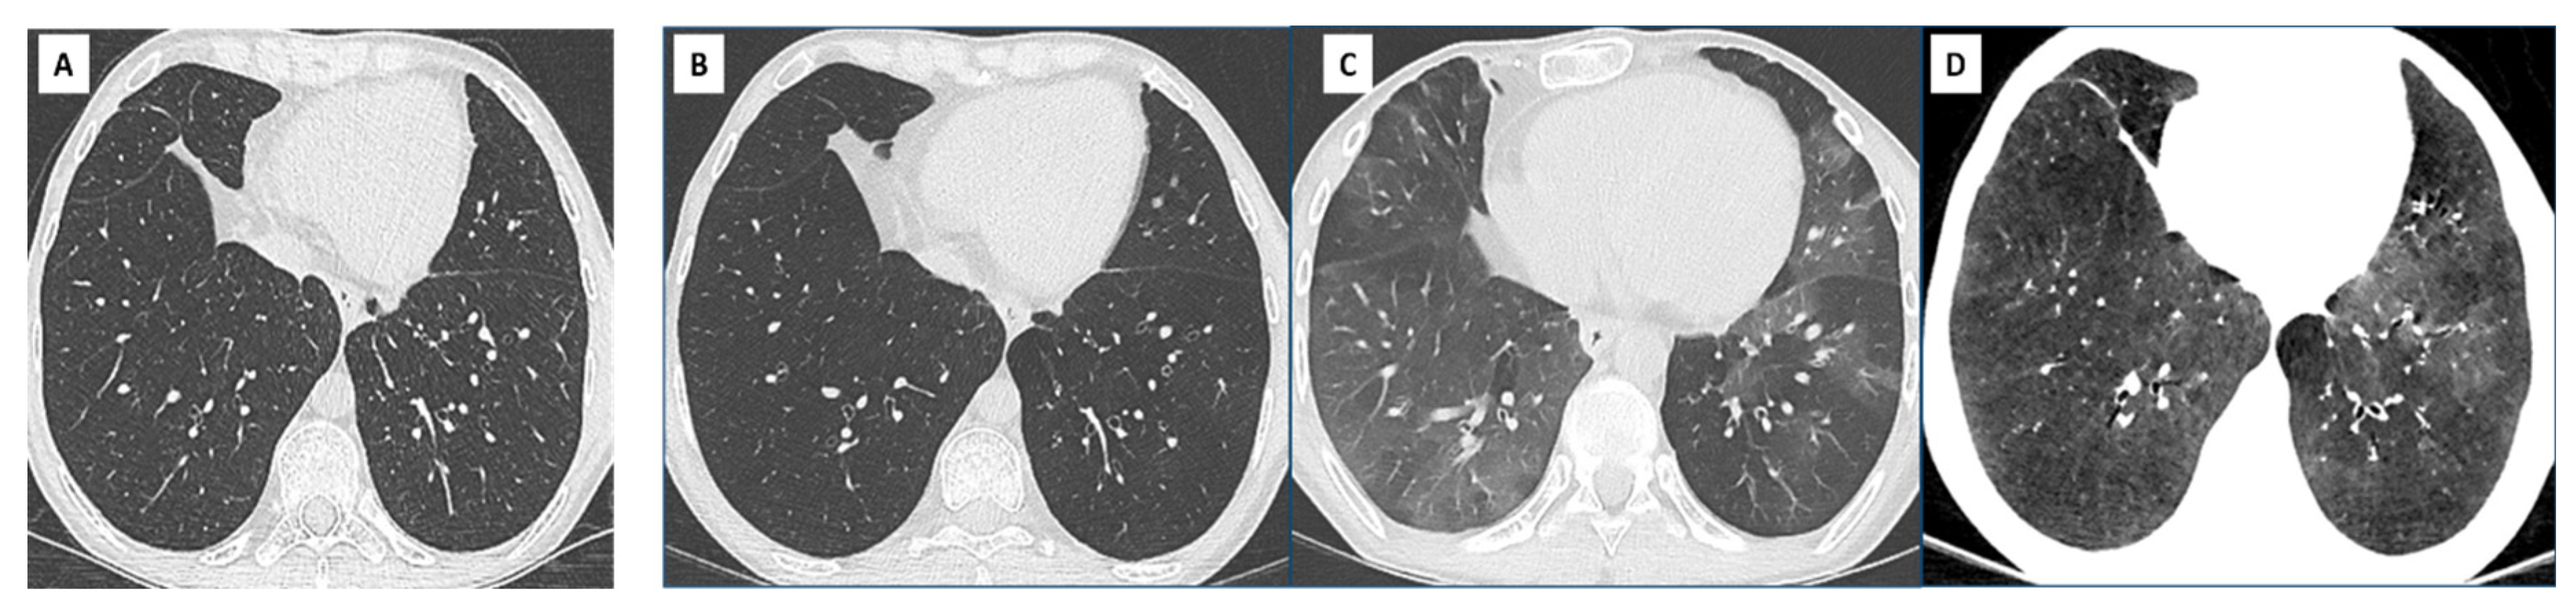

- Hota, P.; Dass, C.; Kumaran, M.; Simpson, S. High-resolution CT findings of obstructive phenotypes of chronic lung allograft dysfunction: More than just bronchiolitis oblierans syndrome. AJR Am. J. Roentgenol. 2018, 211, W13–W21. [Google Scholar] [CrossRef] [PubMed]

- Bankier, A.A.; Van Muylem, A.; Knoop, C.; Estenne, M.; Gevenois, P.A. Bronchiolitis Obliterans Syndrome in Heart-Lung Transplant Recipients: Diagnosis with Expiratory CT. Radiology 2001, 218, 533–539. [Google Scholar] [CrossRef]

- Siegel, M.J.; Bhalla, S.; Guttierrez, F.R.; Hildebolt, C.; Sweet, S. Post-lung transplantation bronchiolitis obliterans syndrome: Usefulness of expiratory thin-section CT for diagnosis. Radiology 2001, 220, 455–462. [Google Scholar] [CrossRef] [PubMed]

- de Jong, P.A.; Dodd, J.D.; Coxson, H.O.; Storness-Bliss, C.; Paré, P.D.; Mayo, J.R.; Levy, R.D. Bronchiolitis obliterans following lung transplantation: Early detection using computed tomographic scanning. Thorax 2006, 61, 799–804. [Google Scholar] [CrossRef]

- Konen, E.; Gutierrez, C.; Chaparro, C.; Murray, C.P.; Chung, T.; Crossin, J.; Hutcheon, M.A.; Paul, N.S.; Weisbrod, G.L. Bronchiolitis obliterans syndrome in lung trnsplant recipients: Can thin-section CT findings predict disease before its clinical appearance? Radiology 2004, 231, 467–473. [Google Scholar] [CrossRef] [PubMed]

- Byrne, D.; Nador, R.G.; English, J.C.; Yee, J.; Levy, R.; Bergeron, C.; Swiston, J.R.; Mets, O.M.; Muller, N.L.; Bilawich, A.-M. Chronic Lung Allograft Dysfunction: Review of CT and Pathologic Findings. Radiol. Cardiothorac. Imaging 2021, 3, e200314. [Google Scholar] [CrossRef] [PubMed]